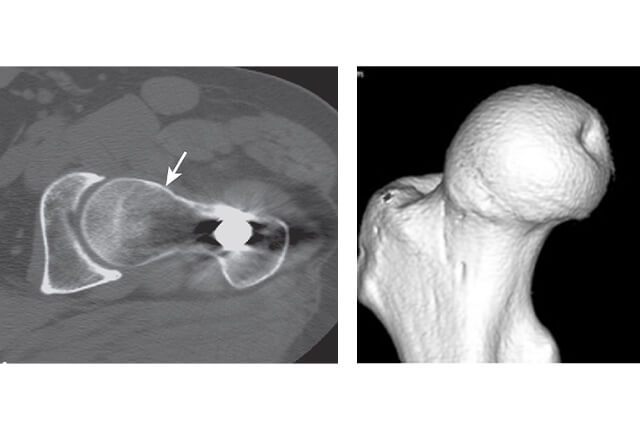

レントゲン、MRI、CT図4

レントゲン、MRI、CT(図4)

大腿骨と寛骨臼が解剖学的異常に基づいて、いわゆる衝突現象(impingement)を起こす病態です。これまで原因不明の変形性股関節症(1次性変形性股関節症)の原因となる病態とされています。